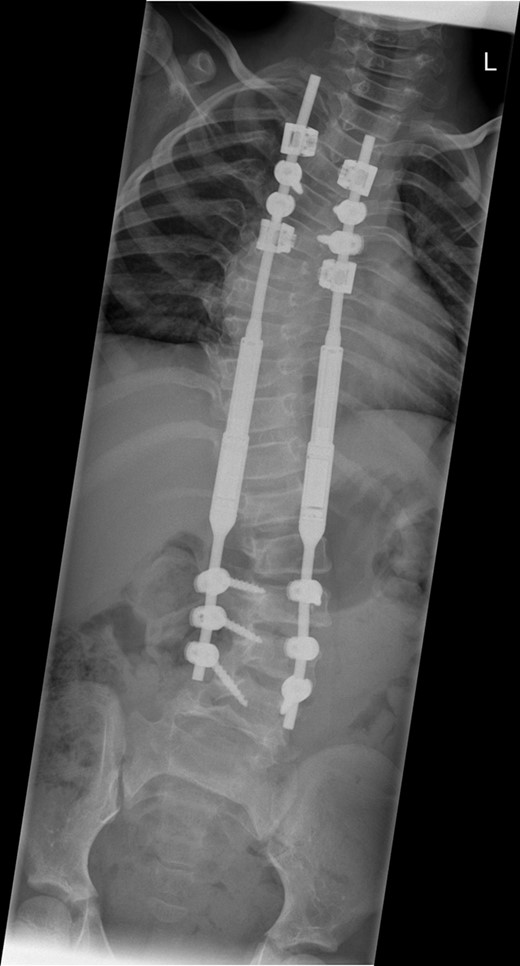

Between the ages of 4 and 6 years, the curve increased rapidly leading to a significant curve measuring 80° in the thoracic spine and 65° in the thoracolumbar spine with a T1–S1 height of 232 mm and T1–T12 height of 150 mm (Fig. 1). A decision was made to intervene operatively and posterior instrumentation with MCGR was performed. Special consideration was given to her bone fragility. Following 4.5 years of bisphosphonate therapy, her last bone mineral density (BMD) assessment by dual energy X-ray absorptiometry before surgery was normal. Her lumbar spine BMD Z-score was +1.5 and the total body less head BMD Z-score was also +1.5. Thus, at age 6 years, a construct of three paired sets of pedicle screws were placed at L2–L4 distally and a combination of pedicle screws at two levels (T4 and T5), with an outer square of sublaminar bands passed under the third and sixth ribs, was placed proximally. The instrumentation used was a 4.5 Expedium System (DePuy Synthes, Raynham, MA, USA) and the Silc Sublaminar Banding System (Globus Medical, Audubon, PA, USA). Post-operative radiographs (Fig. 2) showed good spinal balance and correction of deformity, but fractures of the right 5th and 10th ribs were seen posteriorly at the junction of the rib and transverse process. Following 8 weeks of spinal cast jacket protection, a CT scan showed the rib fractures to have healed. After instrumentation the thoracic curve angle measured 38° and the thoracolumbar curve measured 30°, with a T1–S1 height of 247 mm and a T1–T12 height of 160 mm.

A whole spine radiograph at age 6 demonstrating the double major scoliosis (measuring 80° in the thoracic curve and 65° in the thoracolumbar curve with a T1–S1 height of 232 mm and T1–T12 height of 150 mm).